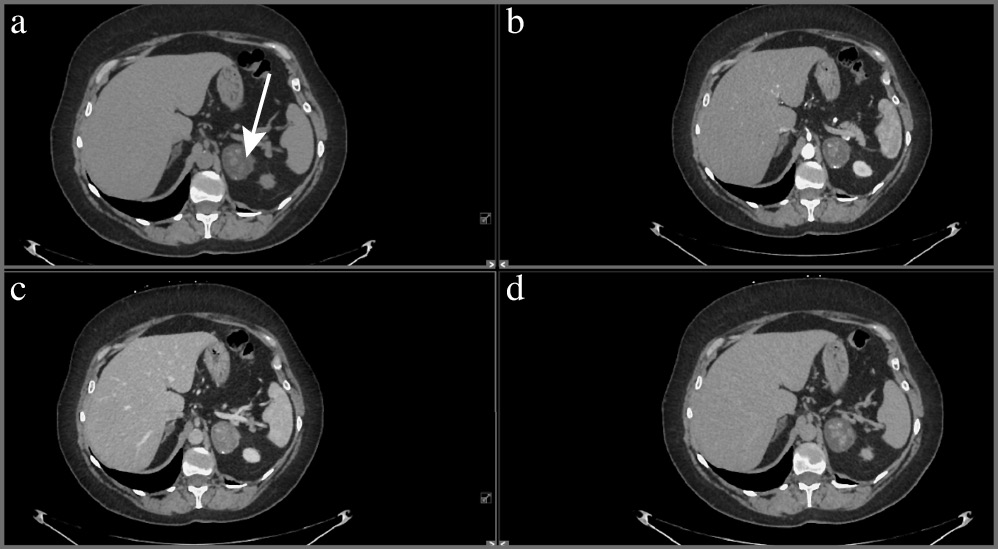

Адренокортикальный рак является наиболее частой первичной злокачественной опухолью, исходящей из коркового слоя надпочечника, и составляет менее 5% всех инциденталом [1]. Как правило, АКР представляет собой крупное образование (от 2 до 40 см, в среднем 11–12 см) с неровными нечеткими контурами, повышенной плотности (более 10 ед. Н). При болюсном контрастном усилении образование умеренно неоднородно накапливает контрастный препарат со слабым его вымыванием в отсроченную фазу. Для данного образования характеры зоны некроза и кровоизлияний, а также кальцинаты, которые встречаются в 30% случаев [16]. При контрастировании возможно обнаружение тонкого капсулоподобного ободка контрастирования (рис. 4) [17]. Необходимо учитывать, что АКР также может быть выявлен в структуре таких доброкачественных образований, как аденомы (в структуре коллизионной опухоли); рис. 5.

Рис. 4. Рак правого надпочечника. МСКТ, аксиальная проекция: а – нативная фаза; b – артериальная фаза; c – венозная фаза; d – отсроченная фаза. В теле правого надпочечника определяется округлой формы образование (стрелка) с четкими ровными контурами, неоднородной структуры, неравномерно накапливающее контрастный препарат.

Рис. 5. Коллизионная опухоль левого надпочечника (рак в структуре аденомы). МСКТ, аксиальная проекция: а – нативная фаза; b – артериальная фаза; c – венозная фаза; d – отсроченная фаза. В левом надпочечнике определяется округлое образование (стрелка) пониженной плотности с четкими ровными контурами, неоднородной структуры за счет наличия мягкотканых включений, интенсивно накапливающих контрастный препарат, со слабым его вымыванием в венозную и отсроченную фазы.

Для АКР характерны признаки злокачественности: инвазивный рост с вовлечением окружающих структур и органов или метастазы. Вовлечение почечной вены (9–19% наблюдений) чаще встречается при опухоли правого надпочечника и проявляется распространением опухоли в просвете данной вены, далее в нижней полой вене до правого предсердия [16, 18].